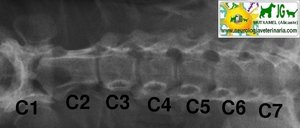

Radiografía columna cervical canina. Proyección latero-lateral |